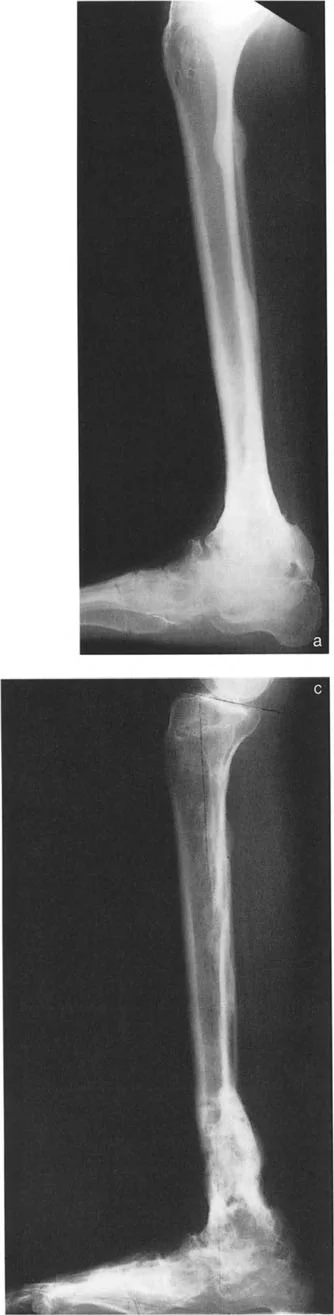

* الكسور غير الملتئمة أو الملتئمة بشكل خاطئ: إذا لم يتم علاج كسر في الجزء السفلي من قصبة الساق أو الكاحل بشكل صحيح، أو إذا حدث التئام للعظم في وضع غير طبيعي، فقد يؤدي ذلك إلى تشوه دائم. على سبيل المثال، كسر في الكاحل يلتئم مع تقوس (Varus) أو روحبة (Valgus) في قصبة الساق يمكن أن يغير ميكانيكا الكاحل بشكل جذري.

* توقف النمو الجزئي: يمكن أن يحدث توقف جزئي في نمو صفيحة النمو بسبب العدوى، أو نقص التروية الدموية، أو بعض الحالات الوراثية، مما يؤدي إلى انحراف العظم مع استمرار نمو الجزء غير المتأثر. في هذه الحالات، يكون مركز دوران التشوه عادةً قريبًا من صفيحة النمو المتأثرة.

* الأشعة السينية (X-rays) الواقفة لكامل الطرف السفلي: هذه الأشعة ضرورية لتقييم المحاذاة الكلية للطرف السفلي تحت تأثير وزن الجسم. يطلب الأستاذ الدكتور محمد هطيف صورًا شعاعية كاملة الطول للساق أثناء الوقوف (Full-length standing alignment films) لتقييم المحور الميكانيكي للساق وتحديد زوايا المفاصل بدقة.

* الأشعة السينية الجانبية والامامية الخلفية للكاحل: تُظهر هذه الصور تفاصيل مفصل الكاحل نفسه، بما في ذلك زاوية القصبة الأمامية البعيدة (ADTA) وزاوية القصبة الوحشية البعيدة (LDTA)، وهي زوايا حاسمة لتحديد التشوه في المستويين الأمامي والسهمي.

أنواع جراحات قطع العظم فوق الكاحل (Supramalleolar Osteotomy)

جراحة قطع العظم فوق الكاحل (SMO) هي الإجراء الأكثر شيوعًا لتصحيح تشوهات قصبة الساق البعيدة. تتضمن هذه الجراحة قطعًا دقيقًا في عظم الساق (القصبة) فوق مفصل الكاحل مباشرة، ثم إعادة محاذاة العظم وتثبيته في الوضع الصحيح. هناك عدة أنواع من هذه الجراحة: